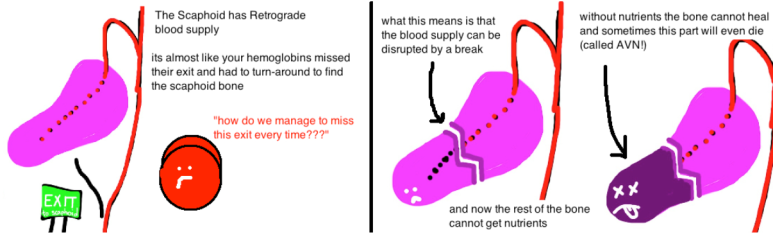

- 주상골은 손목 관절뼈 중 중요한 역할을 합니다. 그런데 골절이 된 이후에는 뼈가 잘 붙지않는 불유합이나, 뼈에 혈액순환이 잘 안되서 뼈가 녹아버리는 골괴사가 발생할 수 있습니다. 이렇게 쉽게 문제가 생기는 이유는 혈류가 적고, 골절 시 혈관손상으로 혈액공급에 문제가 쉽게 발생할 수 있기 때문입니다. 따라서 약간의 뼈의 어긋남이 있어도 뼈가 잘 붙지 않을 수 있습니다.

- 아래 그림에서 골괴사가 잘 되는 이유를 모식도로 잘 설명했습니다. 혈액이 한쪽에서면 공급이되기때문에 골절이 되면 골절된 끝부분의 혈액공급이 잘 안될 수 있기 때문입니다.